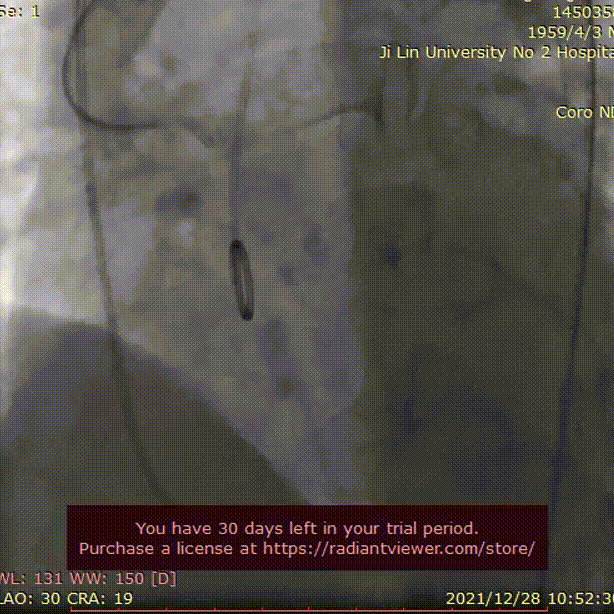

术中影像

主动脉根部造影

20mm球囊充分扩张

瓣膜初始定位

瓣膜逐步释放至工作位

TaurusOne AV26mm瓣膜

瓣下2mm 工作位造影

瓣膜形态良好 位置理想

无瓣周漏